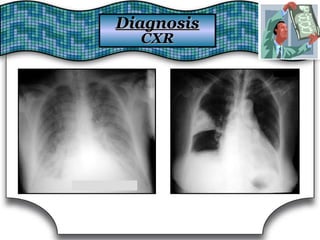

Chest X Ray (CXR)Chest X Ray (CXR)

Chest RadiographChest Radiograph Suggestive DiagnosisSuggestive Diagnosis

Cardiomegaly, increasedCardiomegaly, increased

pulmonary vascular distributionpulmonary vascular distribution

Chronic heart failure, mitral valve stenosisChronic heart failure, mitral valve stenosis

Cavitary lesionsCavitary lesions Lung abscess, TB, necrotizing carcinomaLung abscess, TB, necrotizing carcinoma

Diffuse alveolar infiltratesDiffuse alveolar infiltrates Chronic heart failure, pulmonary edema, aspirationChronic heart failure, pulmonary edema, aspiration

Hilar adenopathy or massHilar adenopathy or mass Carcinoma, metastatic disease, infectionCarcinoma, metastatic disease, infection

HyperinflationHyperinflation COPDCOPD

Lobar or segmental infiltratesLobar or segmental infiltrates Pneumonia, thromboembolism, obstructing carcinomaPneumonia, thromboembolism, obstructing carcinoma

Mass lesion, nodules, granulomasMass lesion, nodules, granulomas

Carcinoma, metastatic disease, Wegener'sCarcinoma, metastatic disease, Wegener's

granulomatosis, septic embolism, vasculitidesgranulomatosis, septic embolism, vasculitides

Patchy alveolar infiltratesPatchy alveolar infiltrates

Bleeding disorders, idiopathic pulmonaryBleeding disorders, idiopathic pulmonary

hemosiderosis, Goodpasture's syndromehemosiderosis, Goodpasture's syndrome